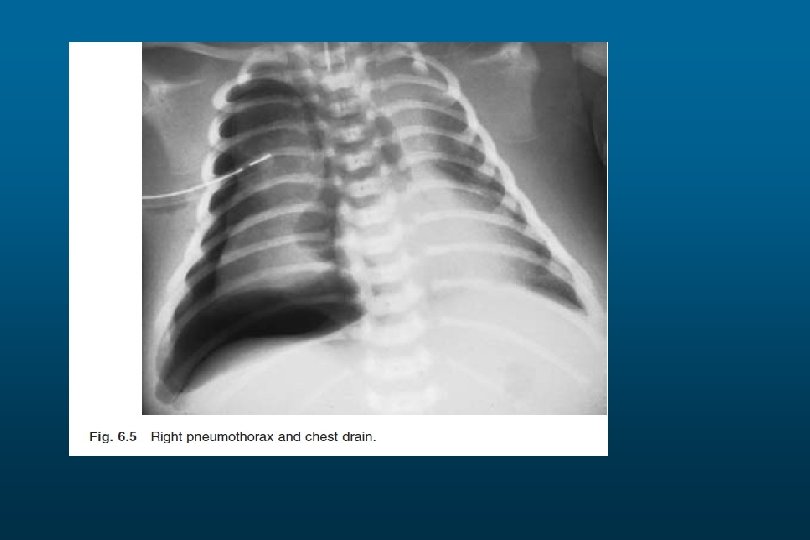

Pneumothorax